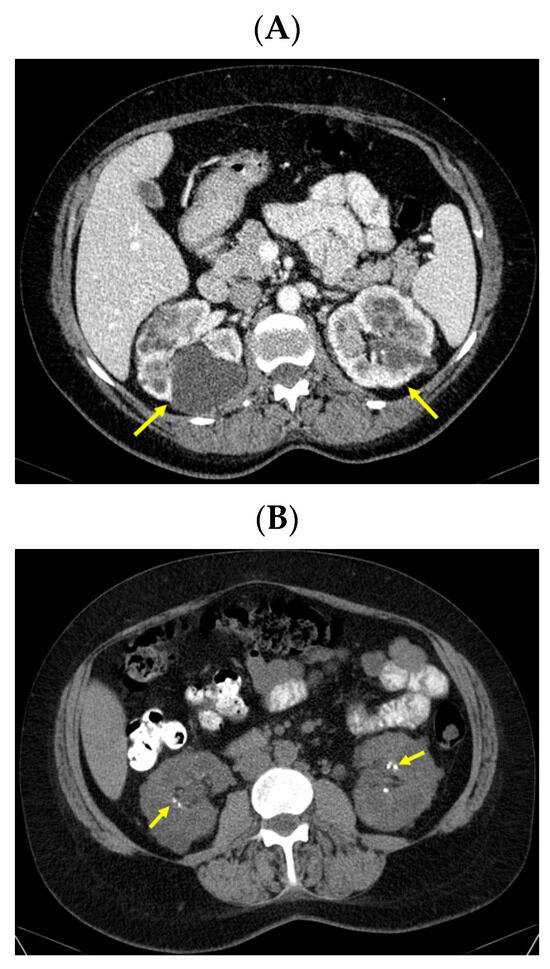

A pelvis CT scan confirmed the osteolytic lesions of the ischium and of the left coxal bone adjacent to the acetabular fossa, measuring 1.97 by 3.29 cm and 1.14 by 1.71 cm, respectively (brown tumors) (Figure 6).

Figure 6.

Pelvis CT scans showing other brown tumors: (A) osteolytic lesion of the left coxal bone adjacent to the acetabular fossa of 1.14 by 1.71 cm (axial plane); (B) osteolytic lesion of the left ischium of 1.97 by 3.29 cm (axial plane).